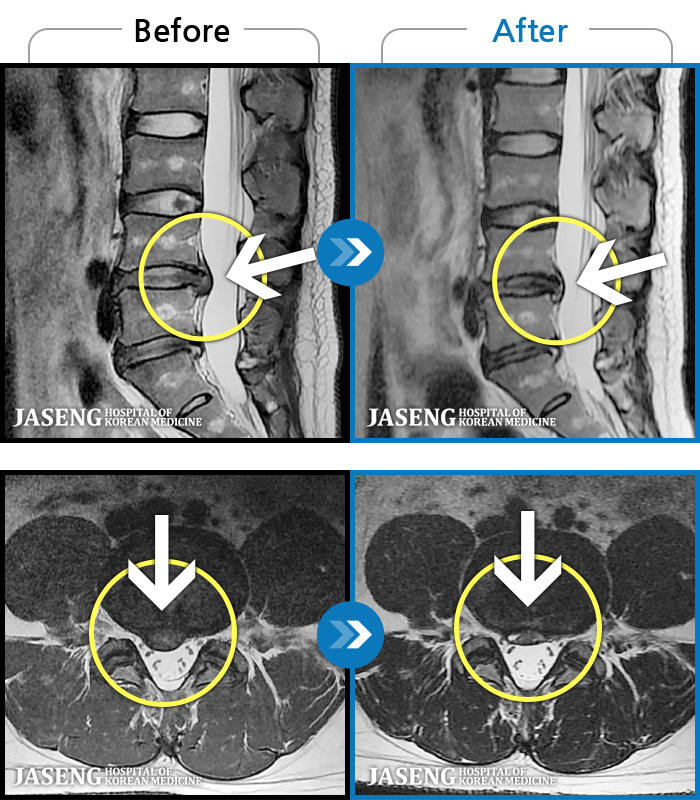

MRI ġ

63 MRI ũ ʸ Ȯϼ.

63

[Կñ:25.02.10~25.09.13]

[Ȼ_㸮ũ] 㸮 ְ ٸ ȱⰡ .